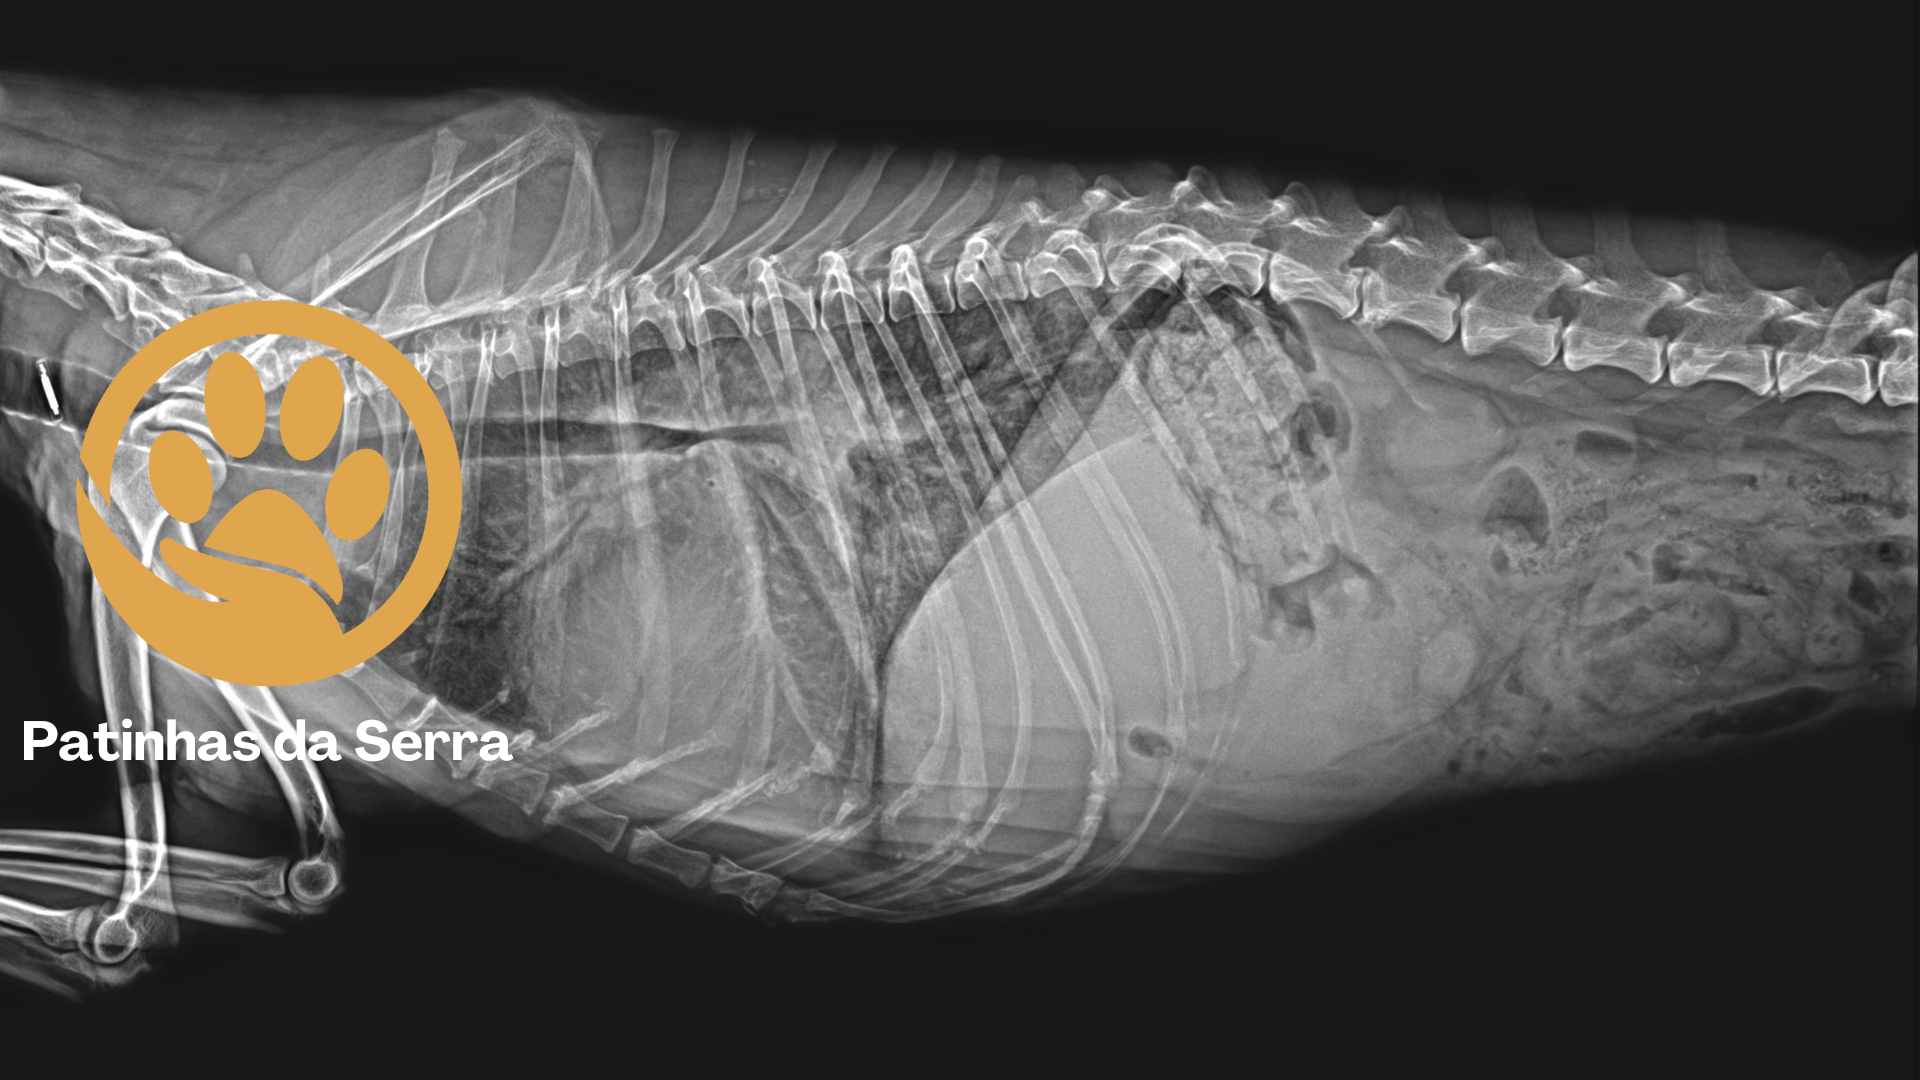

Fornecemos a possibilidade de ajudar a realizar radiografias ao seu patudo, garantido um melhor diagnóstico para várias patologias.